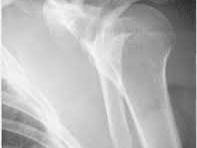

급성기는 대개 손상 직후부터 1주일 안팎까지로, 가만히 있어도 욱신거리거나 자세를 바꿀 때 날카로운 통증이 생길 수 있습니다. 이 시기에는 부종, 멍, 야간통, 누워 자기 어려움이 동반되기 쉽고, 기침이나 몸을 돌릴 때도 통증이 커질 수 있습니다. 이후 2주에서 6주 전후에는 절대 통증이 완전히 사라진다기보다, 진통제와 보조기, 슬링 사용으로 버틸 수 있는 수준으로 낮아지는 경우가 많습니다. 다만 팔을 들어 올리거나 옷을 갈아입는 동작, 세수, 머리 감기, 차량 탑승 같은 일상동작에서는 통증이 쉽게 재발합니다. NHS 계열 안내자료와 정형외과 환자 교육자료들에서는 견갑골 또는 근위 상완골 골절이 대체로 6주에서 12주 사이에 유합되는 것으로 설명하며, 증상은 그보다 더 오래 남을 수 있다고 안내합니다.

문제는 “통증기간”과 “어깨 골절 회복 기간”이 같지 않다는 점입니다. 뼈가 영상에서 붙어 가는 모습이 보여도 어깨 관절은 강직이 오래 남을 수 있고, 특히 위로 뻗는 동작이나 뒤로 손을 보내는 동작은 몇 달 동안 불편할 수 있습니다. 일부 자료에서는 근위 상완골 골절의 회복이 첫 6주에 가장 많이 진행되지만, 어깨 움직임은 3개월 이상 걸릴 수 있고 근력은 1년 가까이 회복 과정을 밟는다고 설명합니다. 견갑골 골절 역시 실제 골절 치유는 3개월 전후까지 보고되며, 근력과 가동범위는 그 후 몇 달 더 회복될 수 있습니다. 그래서 어깨뼈 골절 후 “언제 안 아프냐”는 질문에 대한 가장 정확한 답은, 초기 극심한 통증은 수일에서 수주 내 완화되지만, 움직일 때의 통증과 불편감은 6주에서 12주 이상 이어질 수 있고 완전한 기능 회복은 수개월 단위로 보는 것이 현실적이라는 것입니다.